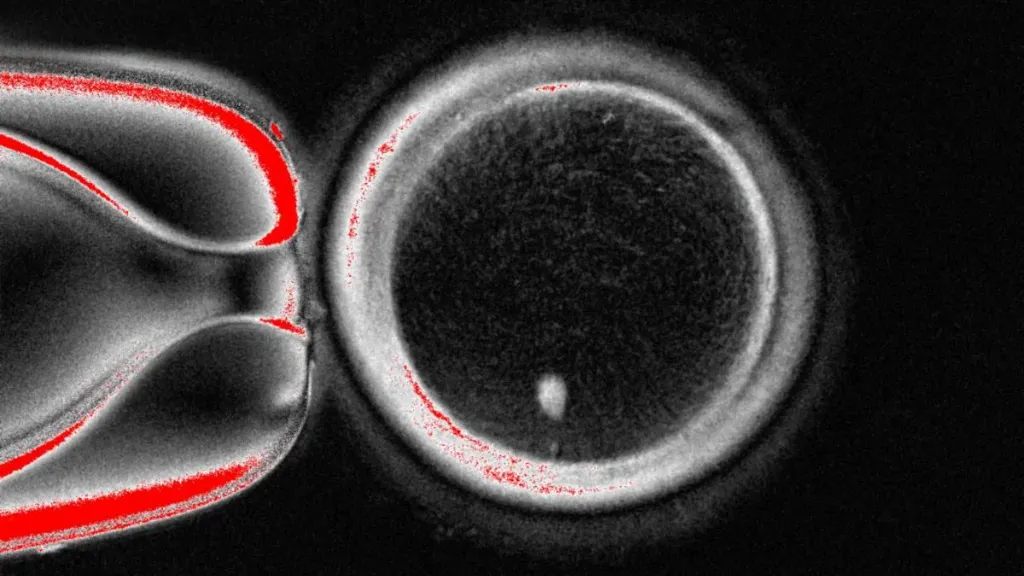

Totuși, ovulul în cauză nu este gata pentru a fi fertilizat de spermatozoizi, deoarece conține deja o suită completă de cromozomi. Un om are în mod normal 46 de cromozomi, organizați în 23 de perechi. Așadar, următoarea etapă este de a convinge ovulul să renunțe la jumătate din cromozomii săi, într-un proces pe care cercetătorii l-au numit “mitomeioză” (este o fuziune între mitoză și meioză, cele două moduri în care celulele se divid).

În cadrul experimentului, au fost produse 82 de ovule funcționale, care au fost ulterior fertilizate cu spermă. O parte din acestea s-au dezvoltat în embrioni care au supraviețuit până la șase zile. Cu toate acestea, procesul mai are mult până să fie gata pentru uz clinic, deoarece ovulul alege în mod aleatoriu cromozomii pe care să îi elimine iar, pentru a preveni apariția bolilor, este necesar să rămână câte unul din fiecare dintre cele 23 de perechi de cromozomi, însă în final rămân câte doi din unele tipuri și niciunul din altele. De asemenea, rata de succes este scăzută (aproximativ 9%), iar cromozomii ratează un proces important în care își rearanjează ADN-ul, numit încrucișare.